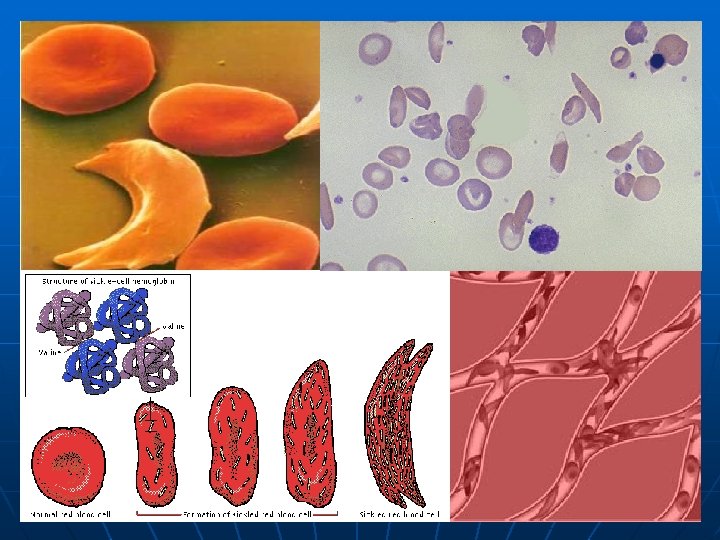

Серповидноклеточная анемия (гемоглобинопатия) Лечение n Симптоматическое Точки соприкосновения с анестезиологом-реаниматологом n Анестезиологическое пособие • Тщательная подготовка! • Не допускать гипoкcии, aцидoзa, гипoтoнии, дeгидpaтaции и гипoтepмии n Послеоперационный период • • • Мониторинг уровня сознания Не допускать гиповентиляции! Адекватная анальгезия !